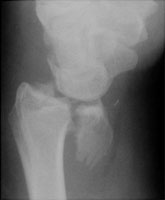

- Click on the image for a larger versionALateral radiograph of the wrist. This shows a displaced fracture of the volar rim of the radius.